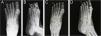

On the radiograph, bone erosion associated with the thickening of soft tissues in the distal phalanx of the left fourth toe was evident (Fig. 2). An excisional biopsy without margins was performed for histological diagnosis.

Anteroposterior (A) and lateral (B) radiographs of the left foot before the surgery: increased soft tissue density and bone erosion of the distal phalanx (blue arrow), resembling a “cup” appearance (B). Anteroposterior (C) and lateral (D) radiographs of the left foot two months after the surgery: partial recovery of bone structure.